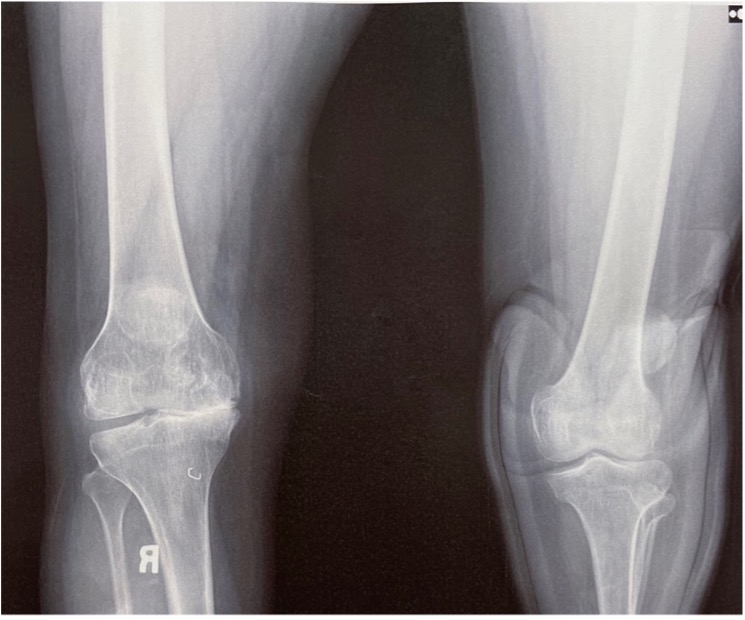

A Post operative picture of lower limbs showing minimal scarring

A Post operative picture of lower limbs showing minimal scarring Scarring In The Knee  Learn the best exercises to break scar tissue in the knee from arthrofibrosis below. Arthrofibrosis is a condition in which you have a buildup of scar tissue around a joint, usually after a traumatic injury or surgical. Hoffa fat pad scarring can be seen as a result of injury and subsequent insufficiency of the acl ligament. Knee scar tissue, also. Scarring In The Knee.

A Post operative picture of lower limbs showing minimal scarring Scarring In The Knee  Learn the best exercises to break scar tissue in the knee from arthrofibrosis below. Repeated compression of the fat pad can cause damage, inflammation, and potentially scar tissue formation. Arthrofibrosis is a condition in which you have a buildup of scar tissue around a joint, usually after a traumatic injury or surgical. Check out these simple, yet effective methods to. Scarring In The Knee.